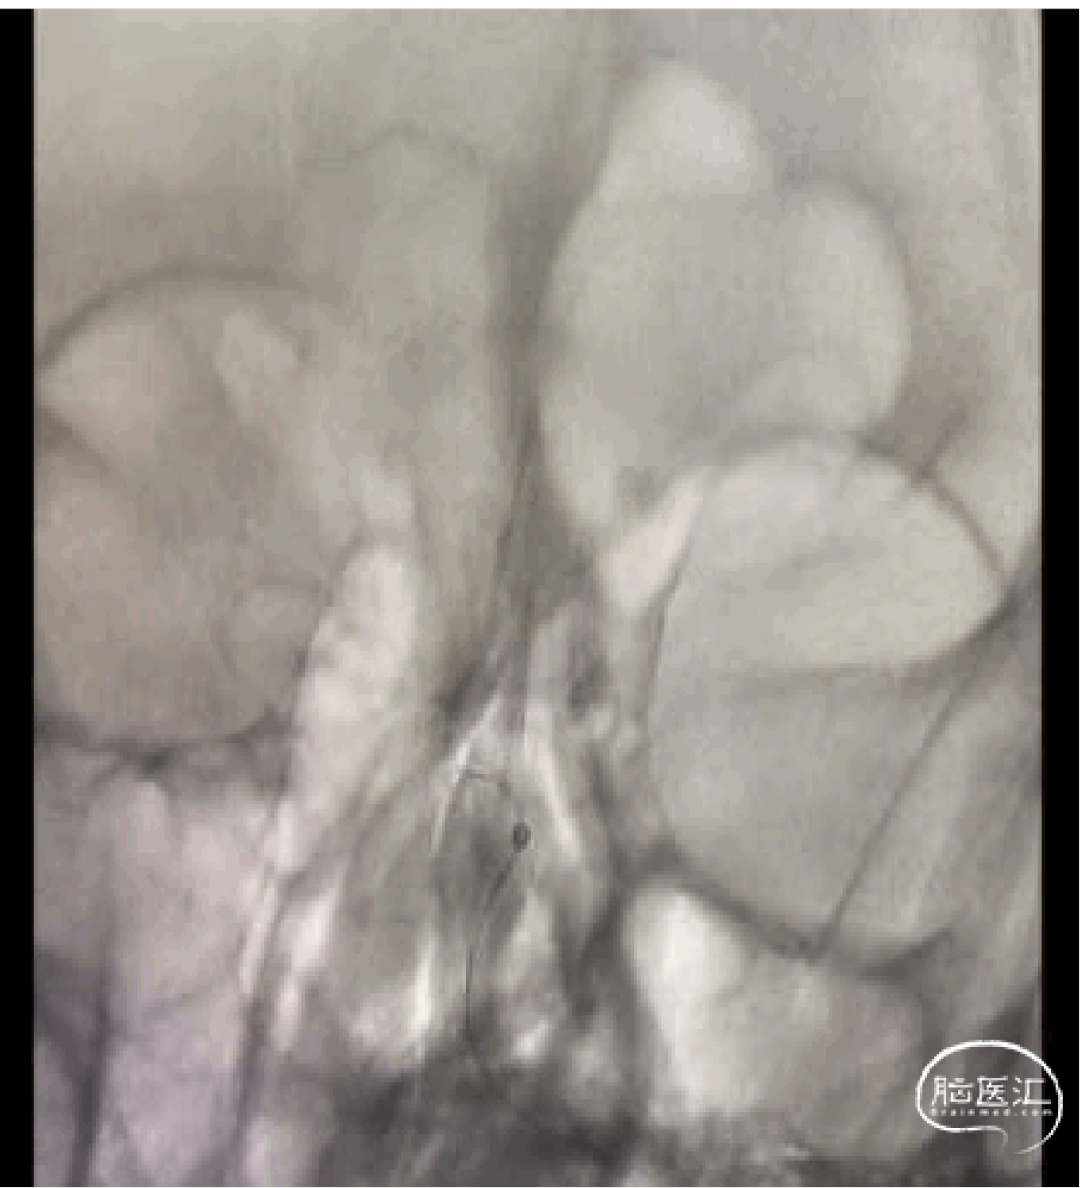

急诊大脑后动脉取栓病例分享

作者:焦伟 冉星堂